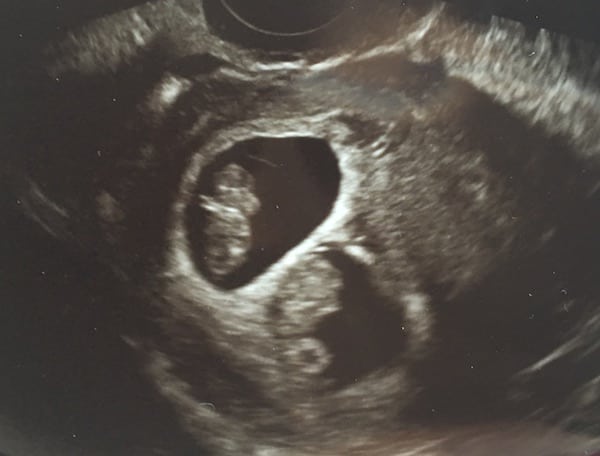

REMINDER: Don’t forget to take a belly shot! 8 week sonogram

Ultrasound Photos – 8 Week Sonogram

8 week sonogra